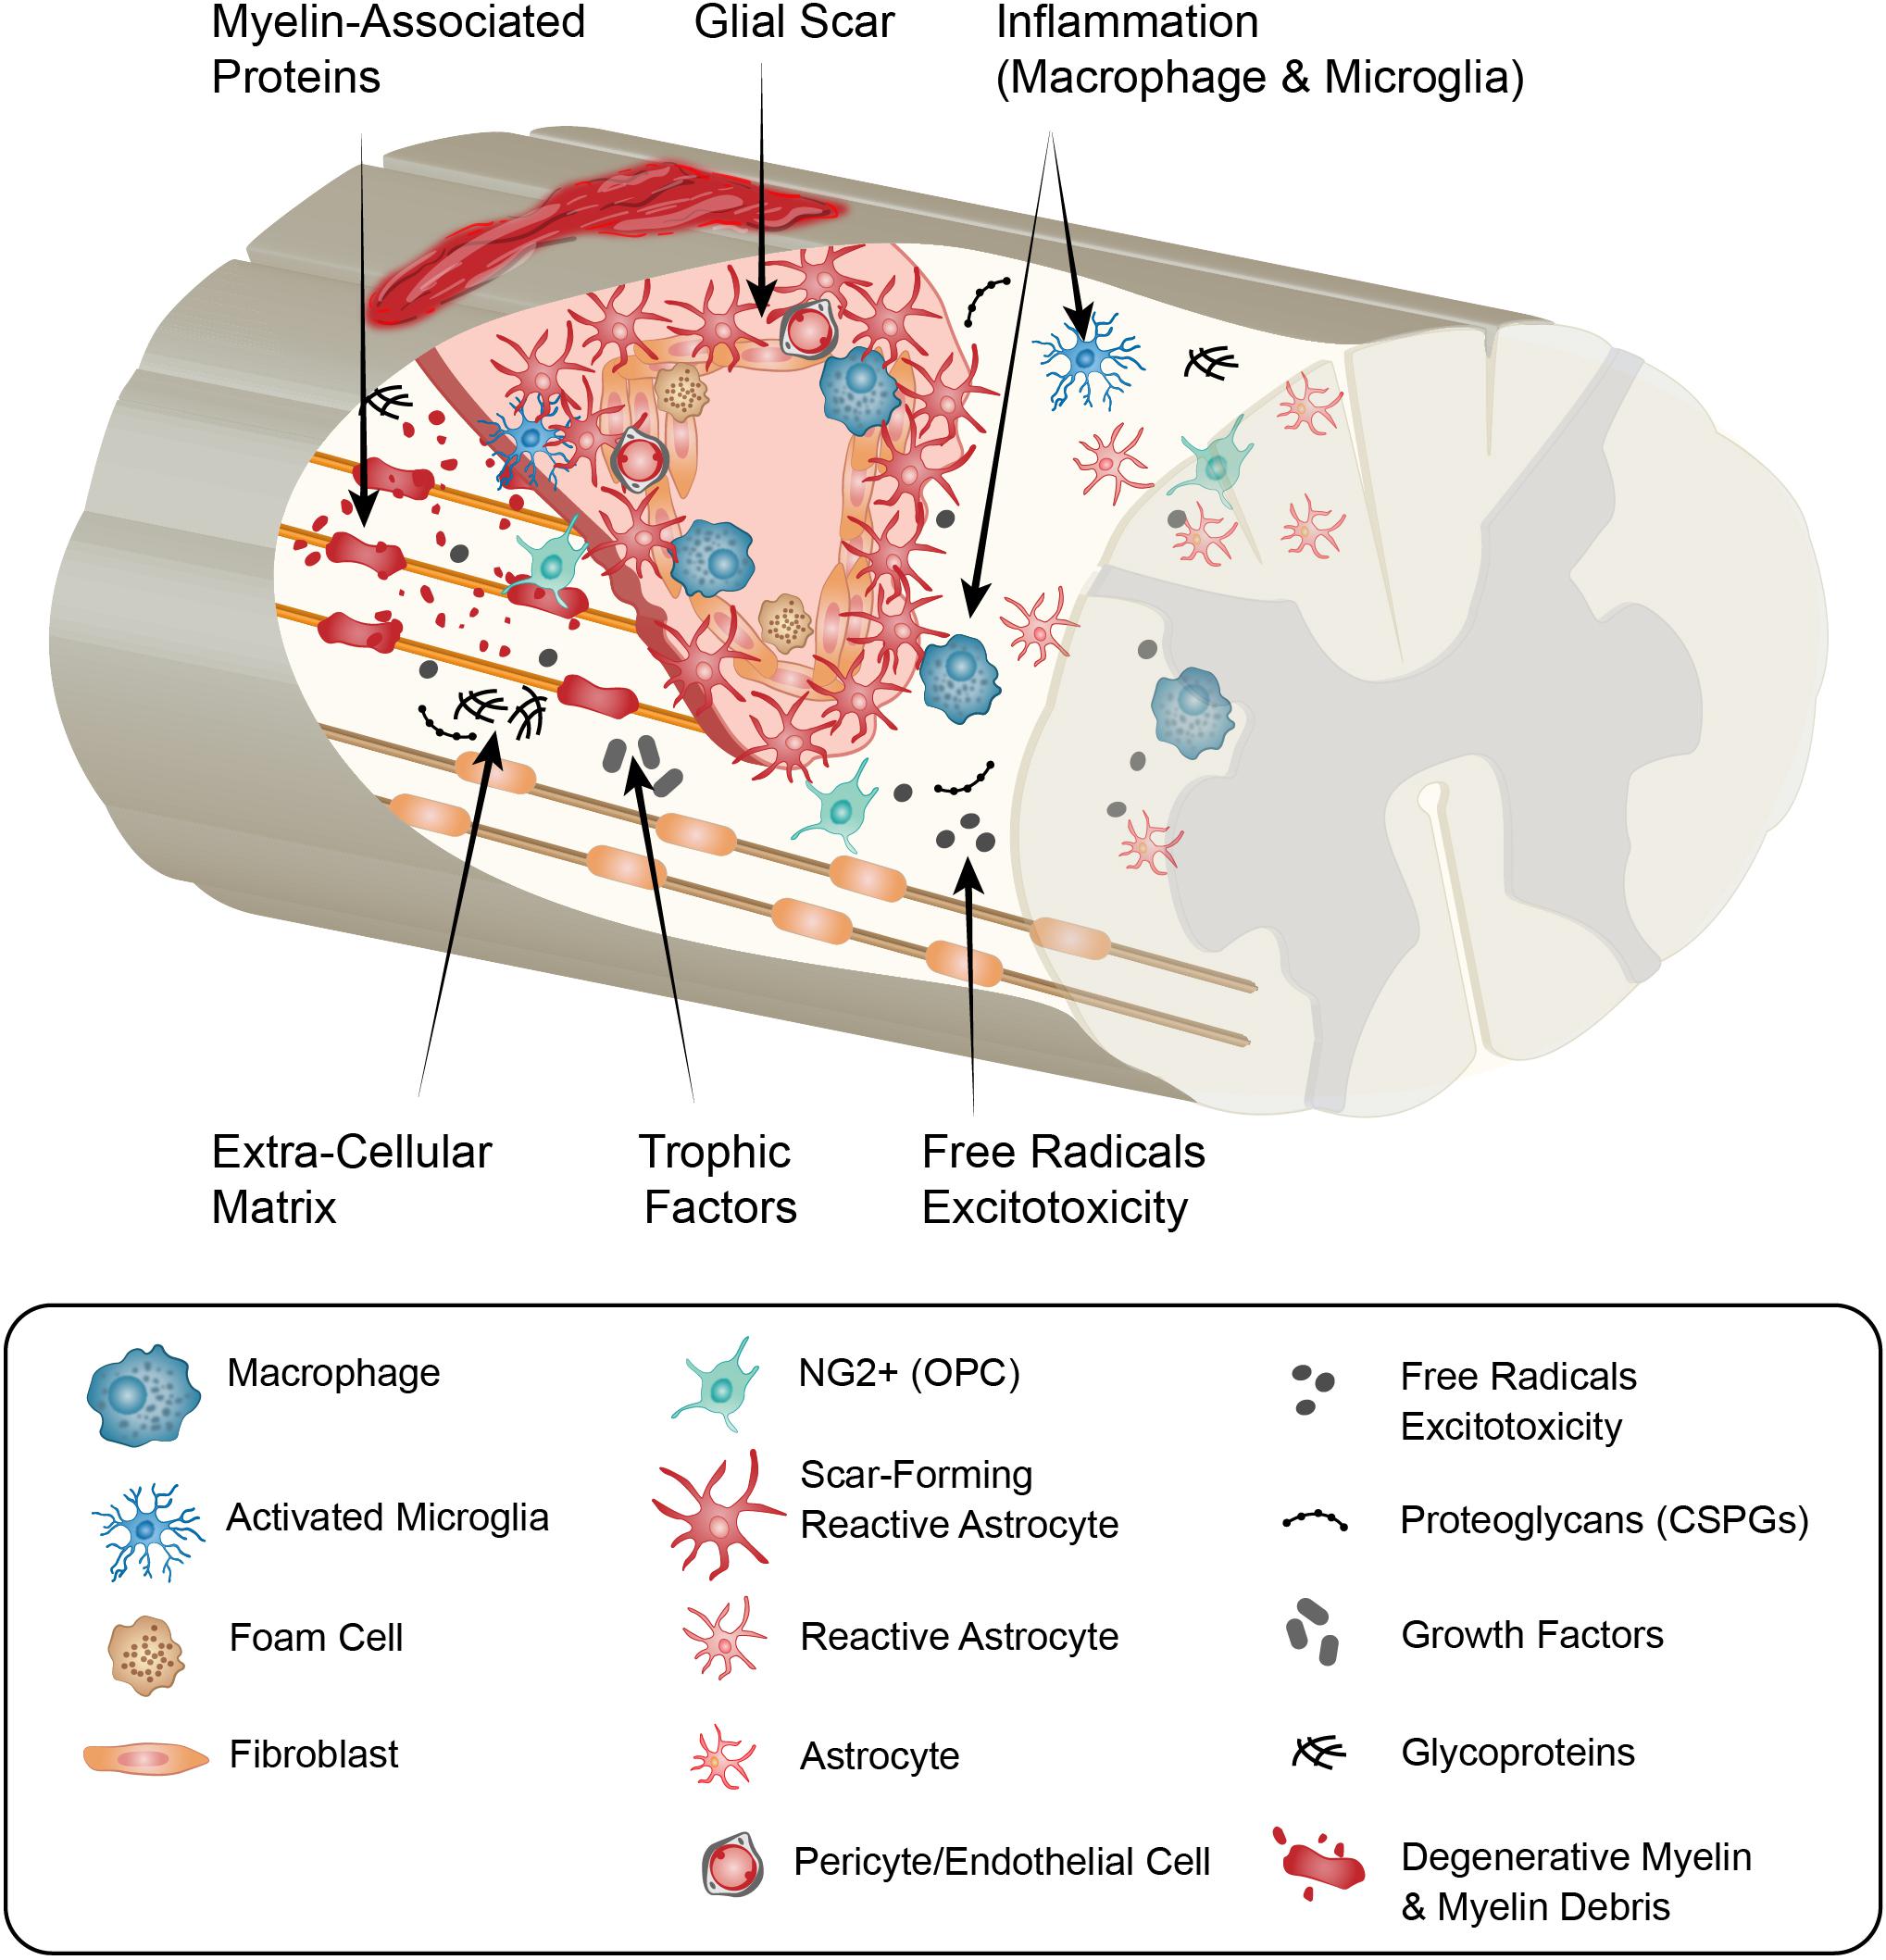

51X8DJl7i5L.jpg_BO30,255,255,。Mobilisation of the Nervous System: 9780443044007: Medicine。Frontiers | The Influence of Neuron-Extrinsic Factors and。Mobilisation of the NERVOUS SYSTEM洋書デイビット・バトラー表紙に細かいスレ傷等、傷み、汚れがあります。【書籍】奇跡を呼ぶ ヒーリングコード。。The Nervous System - An Introduction - Mariska Odendaal。中に書き込みは見当たりませんが、見落としはご了承ください。中古本にご理解の上ご購入ください。Molecular Biology of the Gene (第7版)